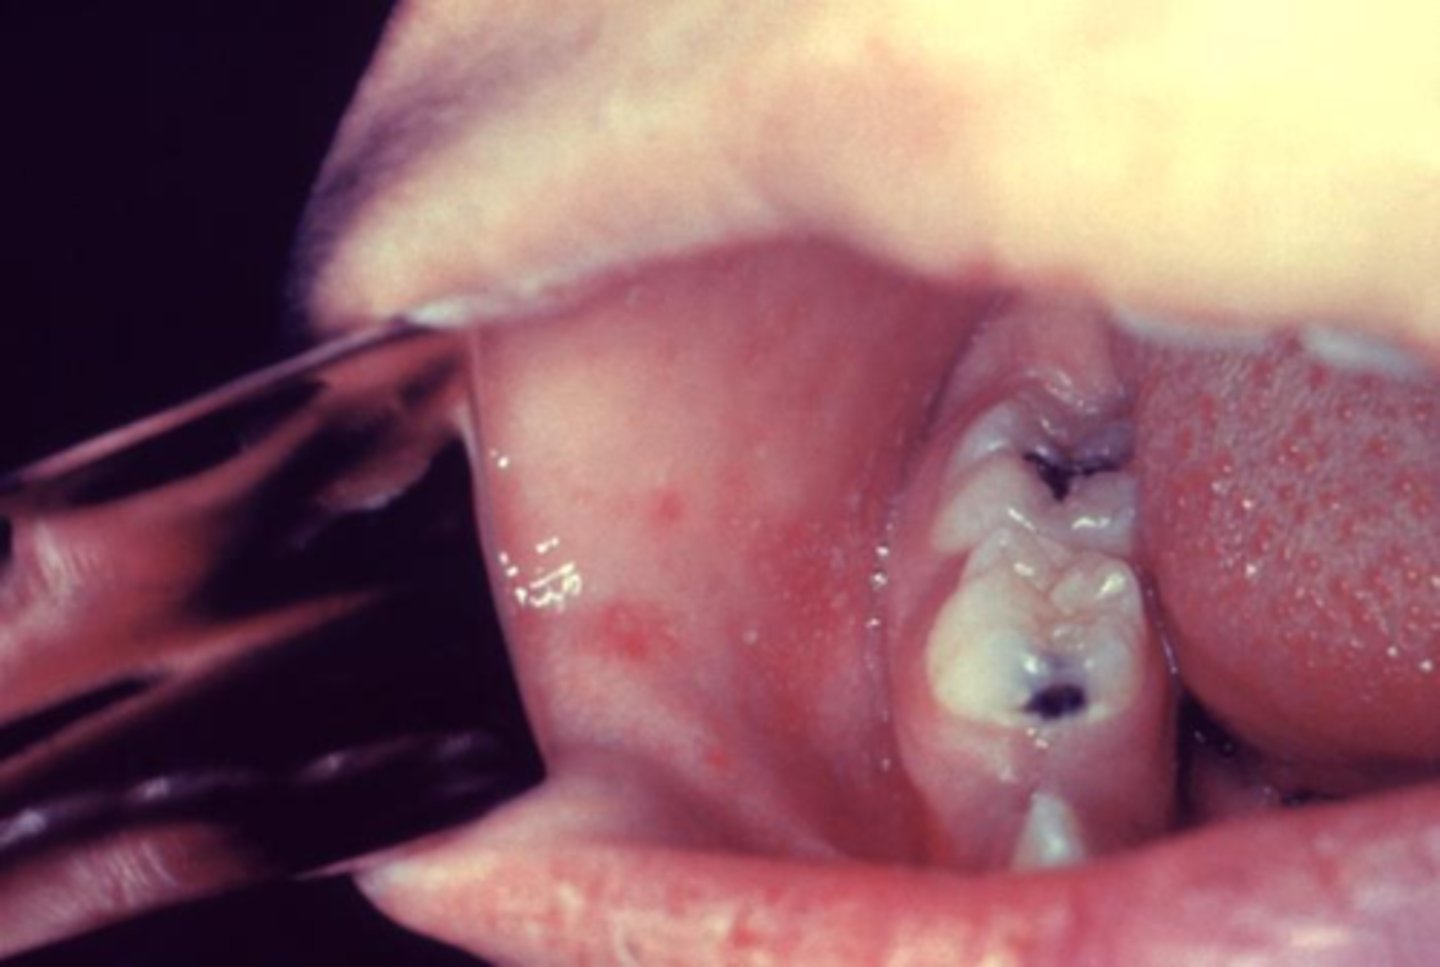

Small, irregular red spots on buccal/lingual mucosa with blue-white centers

Koplik spots (measles, rubeola)

Vitamin A reduces morbidity

Virulence: HA and Fusion protein